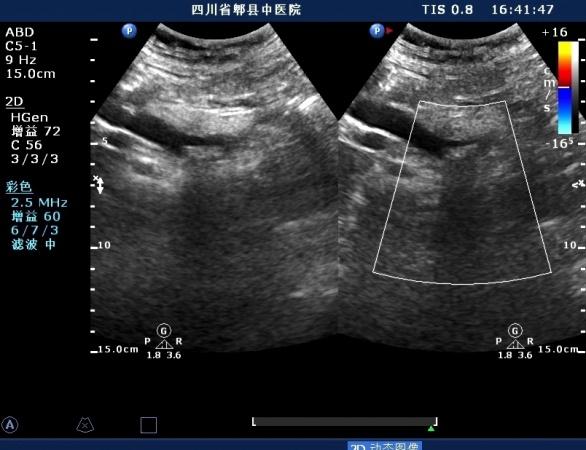

超声如图:胆总管及肝内胆管扩张,呈“平行管征”,胆总管胰腺段可见疏松强回声团堆积,后方可见淡淡声影,左肝外叶胆管内亦可见数个强回声团堆积,后方伴声影。 肝脏及胆总管

胆总管胰腺段结石